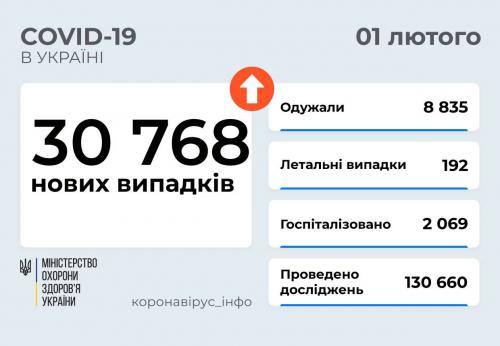

МОЗ: Уперше з початку пандемії було зроблено понад 100 тисяч ПЛР-досліджень за добу

03.02.2022 12:10